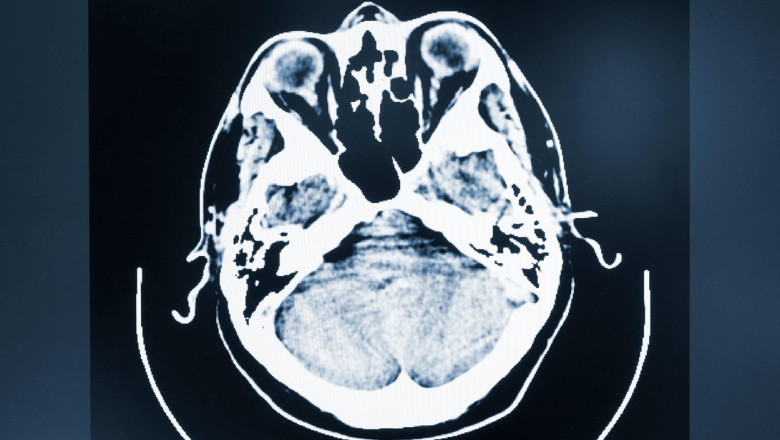

Neuralink spune că este în căutare de pacienţi cu tetraplegie datorată unei leziuni verticale a măduvei spinării sau SLA. Participanţilor le va fi implantat chirurgical un BCI cu ajutorul unui robot brevetat într-o regiune a creierului care controlează mişcarea, cu scopul de a le permite să controleze un cursor de calculator sau o tastatură doar cu ajutorul gândurilor lor. Studiul va evalua siguranţa şi funcţionalitatea tehnologiei, potrivit unui comunicat.